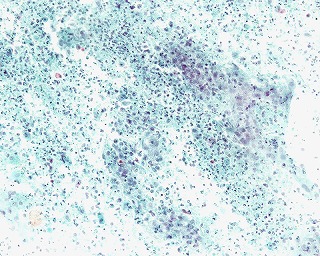

問題 13

材料:子宮筋腫術後断端  年齢:92歳  臨床所見:定期健診